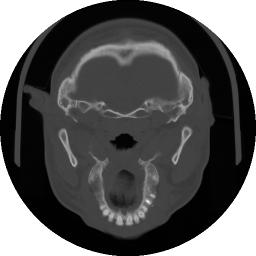

Figura 1‑2 Immagine TAC relativa ad una sezione trasversale del cranio.